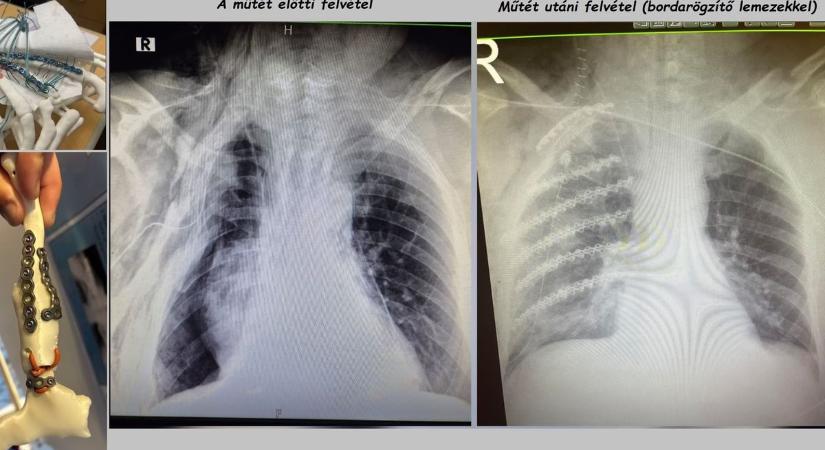

Világszínvonalon látják el a mellkasi sérülteket a győri kórházban